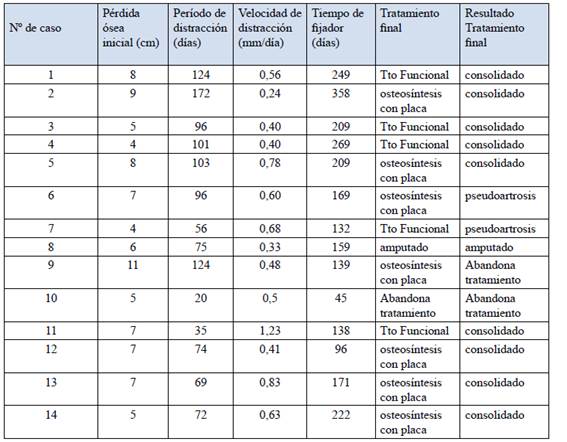

Doce pacientes (86%) tuvieron como patología de ingreso al protocolo pseudoartrosis infectada y en 2 pacientes (14%) fractura expuesta IIIB. Los gérmenes encontrados fueron Staphylococcus Aureus Meticilino Sensible y Meticilino Resistente, Pseudomona Aeruginosa, Acinetobacter, E. Coli y Flora Polimicrobiana a predominio Gram-. La perdida ósea mostró una media de 6,7±2,0 centímetros (mínimo 4 y máximo 11 centímetros).

El período de distracción promedio fue de 92±35 días (entre 35 y 172 días). La velocidad de distracción media fue de 0,58 ± 0,26 mm/día (entre 0,24 y 1,23).

El tiempo promedio de uso de los fijadores fue de 194±70 días desde el inicio de este procedimiento (entre 96 y 358 días).

El tratamiento final consistió en 7 osteosíntesis con placa bloqueada más injerto óseo, 5 compresión más injerto óseo terminando con tratamiento funcional, 1 paciente abandonó el tratamiento luego de la osteotomía y 1 amputado. (Tabla 2)

Consolidaron 69,2% (9 de 14 pacientes), 5 de los 7 con osteosíntesis con placa bloqueada y 4 de los 5 con tratamiento funcional; en 2 pacientes no se logro la consolidación del sitio de acoplamiento resultando una pseudoartrosis aséptica, uno para osteosíntesis con placa y otro para tratamiento funcional; 1 paciente con osteosíntesis con placa abandonó el tratamiento luego de la cirugía.

Referente a la tasa de infección no hubo ninguna recidiva de la misma, ni infección del sitio de osteotomía.

Los resultados óseos según la clasificación de Paley fueron: 6 excelentes, 3 buenos, y 2 malos; en tanto para la valoración funcional fueron 5 excelentes, 4 buenos y 2 malos, 3 abandonaron el tratamiento.

La evaluación de satisfacción de los pacientes para el tratamiento y el resultado final mostró un nivel de muy satisfecho en 6 pacientes, 3 satisfecho, en tanto 2 pacientes se manifestaron insatisfechos dado que no se logro la consolidación del sitio de acoplamiento.

Las complicaciones fueron: una fractura del hueso neoformado que se trató ortopédicamente con buena consolidación, y desaxación del fragmento de bala que requirió luego una osteotomía de realineación en 3 pacientes, al no poder manejar el varo-valgo y retro-antecurvatum con estos fijadores y el resultado final en estos casos fue excelente. Un paciente presentó rotura del implante (placa DCP), se reintervino y se colocó placa bloqueada más injerto autólogo logrando la consolidación. Se presentaron 4 casos de infección superficial de los Schanz, que se resolvieron con antibióticos vía oral.